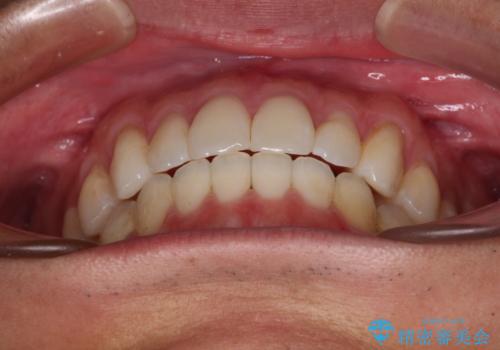

少しでも口元を閉じやすく インビザラインによる前突の解消

- 全体的なデコボコと、前歯の前に出ている感じを気にして来院された患者様です。

患者様と相談の上、非抜歯にてインビザラインを用いて矯正治療を行うこととし、IPR(歯と歯の間)並びに歯列全体の後方移動により口元の突出感の改善することとしました。

お仕事が忙しい方で、装着時間が不足したり、定期的な通院ができなかったりと、自己管理が重要なインビザラインによる矯正治療が長期化する要因が重なり、5年ほどの期間を要しました。